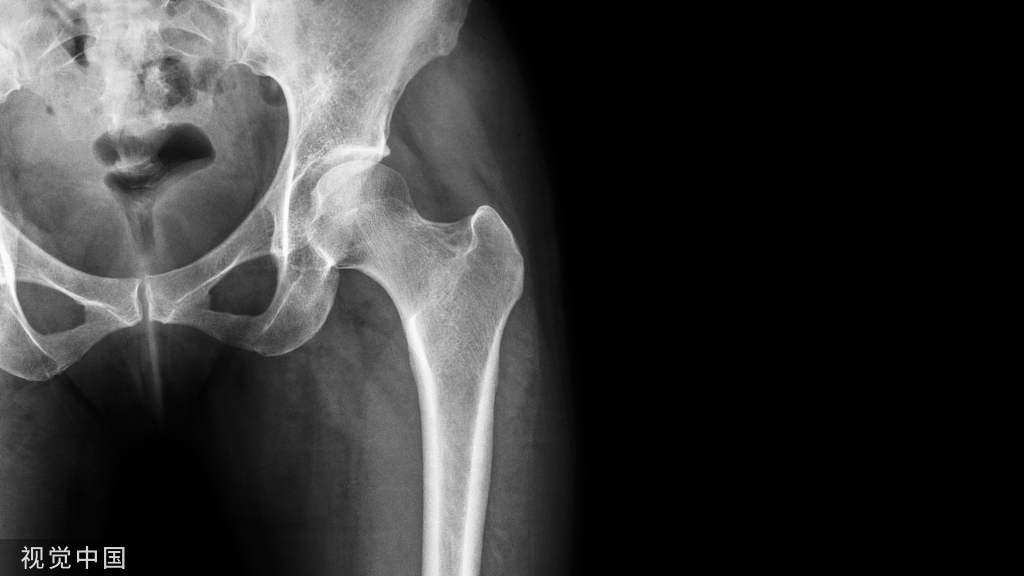

影像学检查X线片:股骨头位于髋臼的外上方、有无合并髋臼后缘骨折X线表现:后脱位股骨头变小,股骨头变大。后脱位时,小转子有可能因为肢体的内旋而不可见。前脱位时,小转子可因肢体的外旋而全部显现。